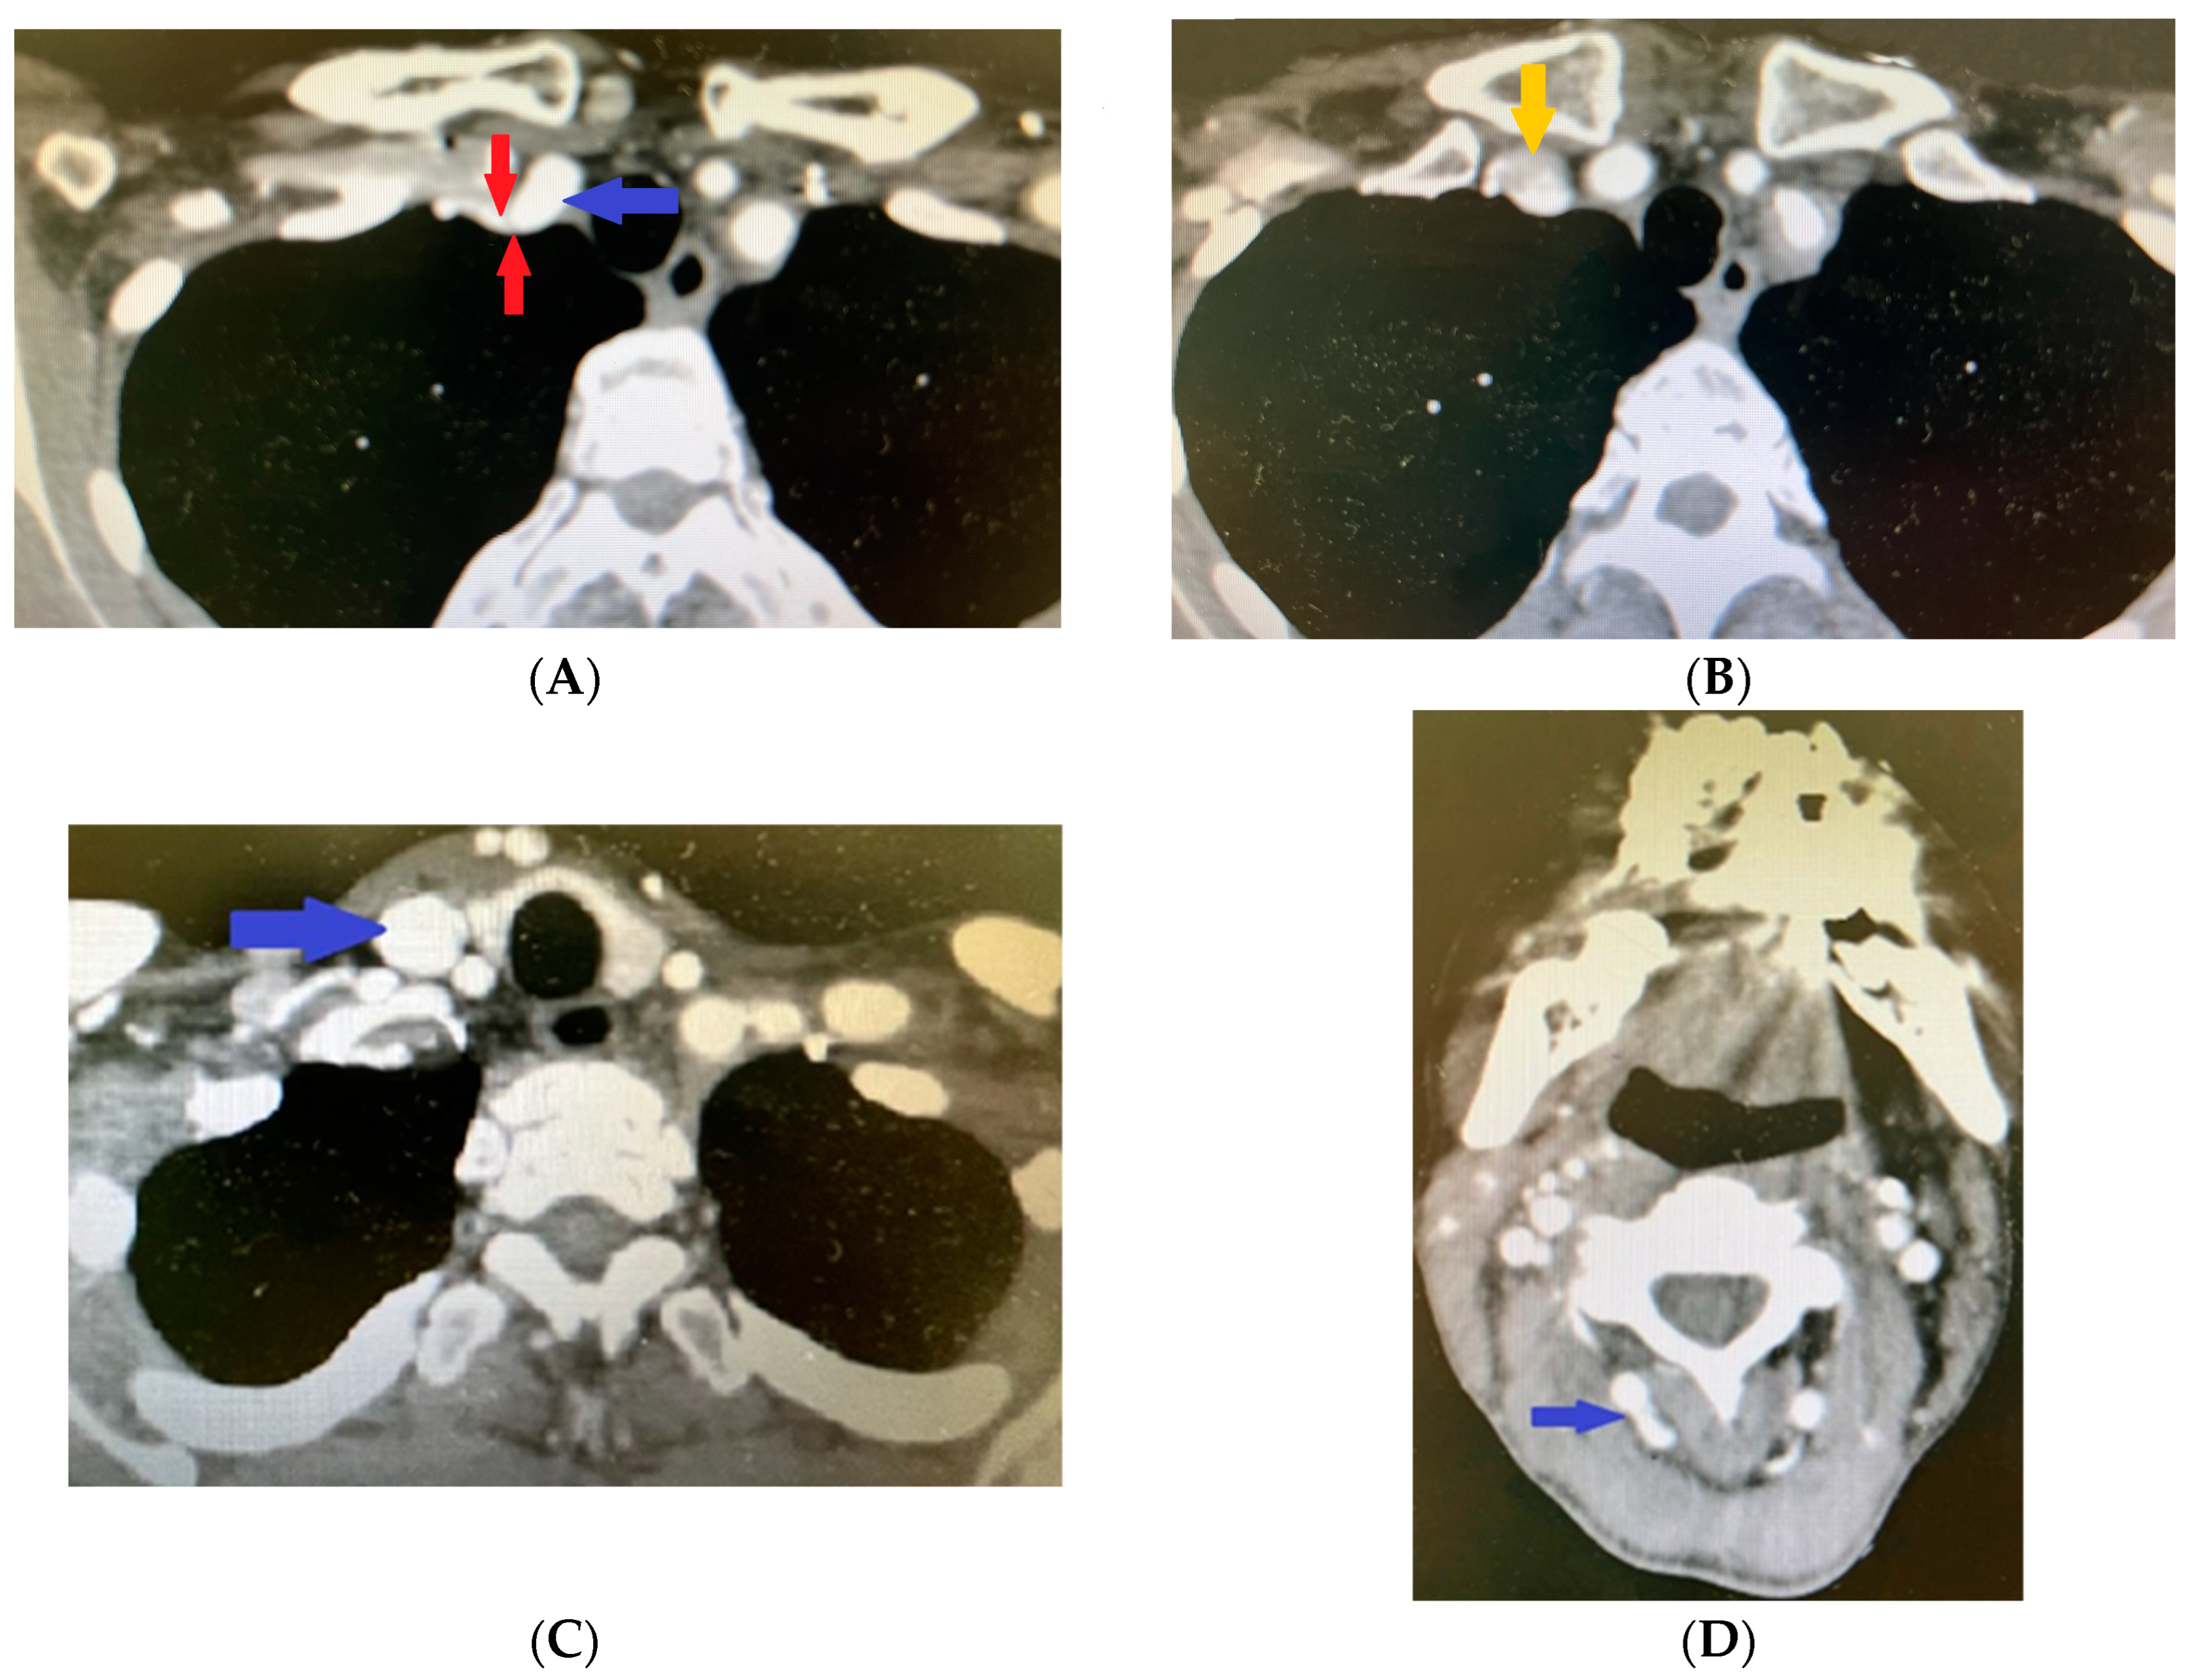

2. Clinical Case Presentation